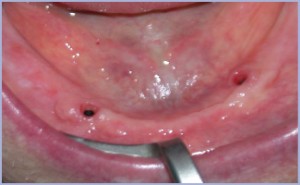

Paziente maschile di 83 anni. Si presentava alla nostra osservazione con edentulia totale di entrambi i mascellari (fig. 1), già portatore di protesi totale rimovibile e con la chiara esigenza di rifare la protesi inferiore a causa della mancanza di stabilità .

- Fig. 1